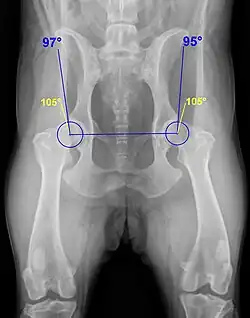

Ein wesentliches Auswertungskriterium ist der Norberg-Winkel. Er ist als der Winkel definiert, der zwischen der Verbindungslinie der Zentren der beiden Oberschenkelköpfe und dem jeweiligen vorderen Pfannenrand abgetragen wird (siehe Abbildung). Bei einem HD-freien Tier sollte er mehr als 105° betragen (gelbe Linien).[3]

| A | HD-Frei | In jeder Hinsicht unauffällige Gelenke, Norberg-Winkel 105° oder mehr. Manchmal noch A1 wenn der Pfannenrand den Oberschenkelknochen noch weiter umgreift. | 25 % |

| B | HD-Verdacht | Schenkelkopf oder Pfannendach sind leicht ungleichmäßig und der Norberg-Winkel beträgt 105° (oder mehr), oder Norberg-Winkel kleiner als 105° aber gleichförmiger Schenkelkopf und Pfannendach. | 33 % |

| C | Leichte HD | Oberschenkelkopf und Gelenkpfanne sind ungleichmäßig, Norberg-Winkel 100° oder kleiner. Eventuell leichte arthrotische Veränderungen. | 27 % |

| D | Mittlere HD | Oberschenkelkopf und Gelenkpfanne sind deutlich ungleichmäßig mit Teilverrenkungen. Norberg-Winkel größer 90°. Es kommt zu arthrotischen Veränderungen und/oder Veränderungen des Pfannenrandes. | 11 % |

| E | Schwere HD | Auffällige Veränderungen an den Hüftgelenken (beispielsweise Teilverrenkungen), Norberg-Winkel unter 90°, der Pfannenrand ist deutlich abgeflacht. Es kommt zu verschiedenen arthrotischen Veränderungen. | 4 % |